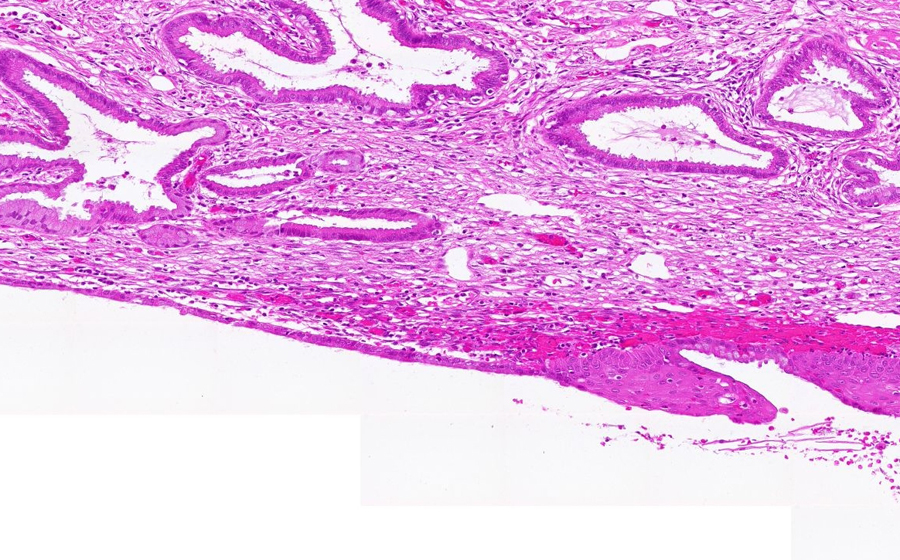

Slide 3: Chronic cervicitis and metaplasia

Histologic section of cervix from a patient with chronic cervicitis (click here to review normal tissue)

Image 2 - 50X

Slide 3 - Image 2